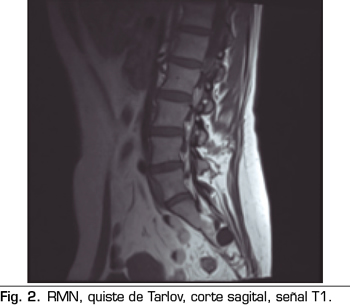

Los “quistes perineurales” o “Quistes de Tarlov” son alteraciones en la duramadre de las raíces nerviosas, que se producen más frecuentemente en la zona sacra. El diagnóstico suele ser casual mediante RMN; la incidencia es variable, debido a que el hallazgo es incidental. Habitualmente son asintomáticos, pero pueden producir radiculopatía, dolor perineal o vejiga neurógena, entre otros.

Figura 1